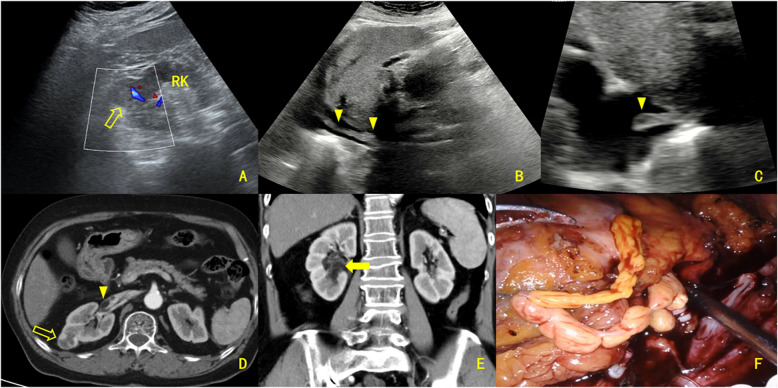

Results: Enhanced CT showed renal sinus involvement in all CAML cases versus four ccRCC cases (p = 0.002). All primary CAML tumors had fatty components, compared to one ccRCC case (p < 0.001). Enhanced CT also revealed 7 VTTs with fatty components (6 in the CAML group) (p < 0.001). Thrombus lengths in the inferior vena cava (IVC) were 8.05 ± 2.22 cm for CAML and 5.29 ± 2.38 cm for ccRCC, with no significant difference (p = 0.610). The maximum/minimum anteroposterior VTT diameter ratios were 3.98 and 1.09, respectively (p < 0.001); coronal diameter ratios were 4.00 and 1.12, respectively (p < 0.001). Ultrasound revealed that, except for one Mayo Level 0 case, the involved IVC in the CAML group had continuous, intact walls with blood flow signals in the residual lumen, while in the ccRCC group, most VTTs had unclear boundaries and only one case showed blood flow signals in the residual lumen (p = 0.001). Intraoperative blood loss was significantly lower in CAML cases (p = 0.017). No CAML patient had VTT invading the venous wall, unlike 8 ccRCC patients (p = 0.016). All patients were followed for 21-74 months (median: 34.5 months, mean: 36.6 months). All were alive with normal renal function, and no tumor recurrence or metastasis was observed.

Conclusion: Renal CAML with VTT is characterized by three imaging features: the presence of fatty components, a unique geometric growth pattern, and the absence of venous wall invasion, potentially serving as valuable indicators for differentiating CAML from ccRCC lesions.